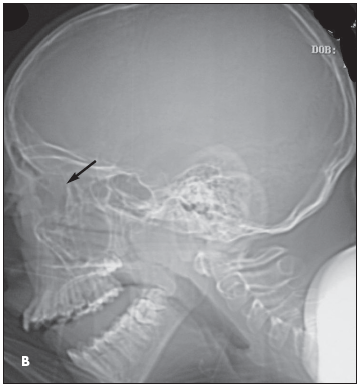

Intraorbital abscess: The radiographs demonstrate opacity of the ethmoid air cells on the left (A and B, blackarrows) with increased opacity of the left maxillary antrum, which is best seen on the frontal view (A, red arrow). The sphenoid and frontal sinuses are unremarkable. The increased density seen on the films results from the filling of the normally aerated sinuses with opaque material (in this case, mucus).

Coronal (C) and axial (D) CT images confirm the radiographic findings of opacity of the ethmoid air cells (red arrows) and maxillary antrum (black arrow) caused by mucus and fluid. These images also define the extent of orbital edema and proptosis (yellow arrows).